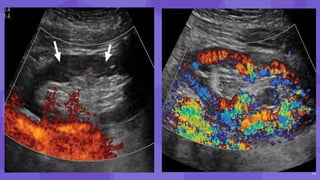

• #14 Immediate postoperative power Doppler image of the left iliac fossa transplant kidney shows complete absence of cortical flow (arrows). Immediate The patient was returned to the operating room and the allograft was intraperitonealized, CASE OF compartment syndrome due to fascial compression. (b) Follow-up color Doppler image of the kidney shows good cortical flow.